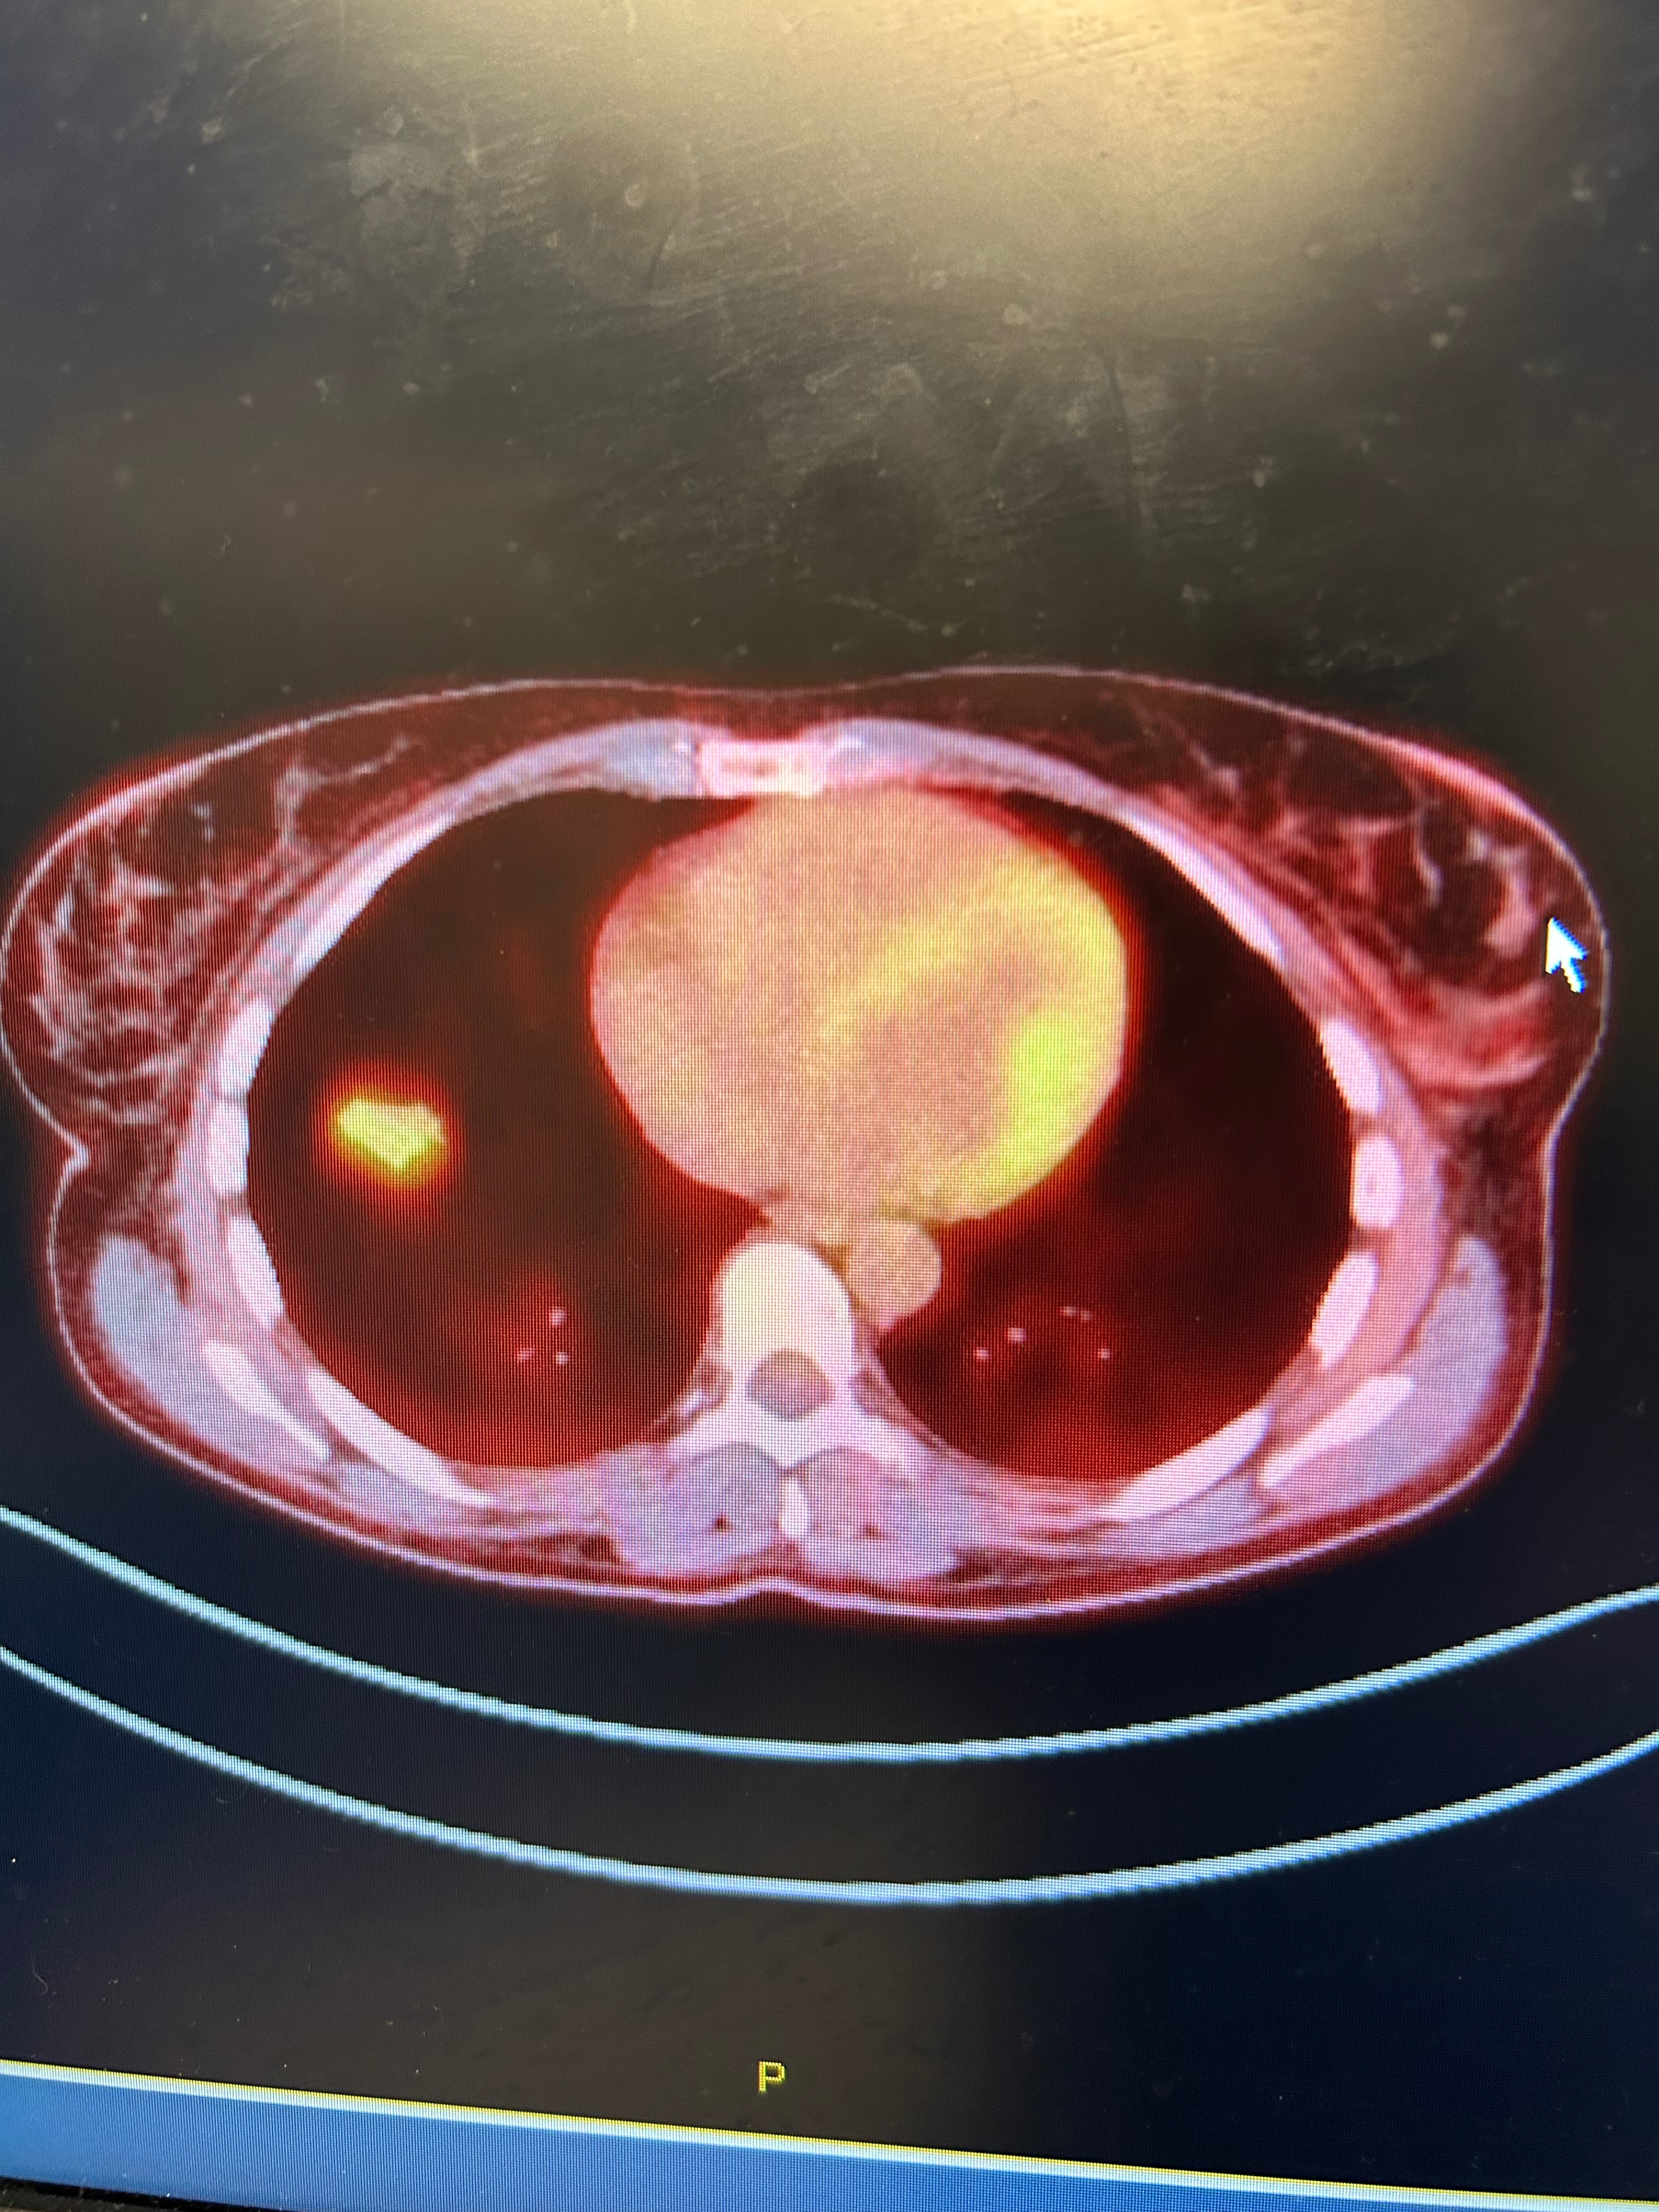

We're reaching out on behalf of this incredible mom of three who has just received a life-changing diagnosis: a rare form of lung cancer at just the young age of 45 years old.

As she faces this battle with courage and strength, she’s preparing for her first major surgery, (removing the lower lobe of her right lung). This will require at least a 3-month recovery period, meaning this time out of work, mounting medical expenses, not covered by insurance and the challenge of caring for her youngest child who has special needs during this difficult time.